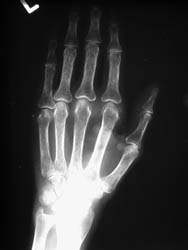

CPPD disease causes destruction of cartilage which can lead to radiographic

findings similar to osteoarthritis. Sites of involvement are useful for differentiating

the two since the radiocarpal compartment of the wrist is not a common location

for osteoarthritis. Lack of an erosive process at the MCP joint differentiates

CPPD crystal deposition disease from rheumatoid arthritis. Greater propensity

for the MCP joints (also commonly includes the 4th and the 5th) with medial

beak-like osteophytosis at the metacarpal heads and more widespread involvement

of the carpal bones may help to differentiate hemochromatosis from idiopathic

CPPD disease.